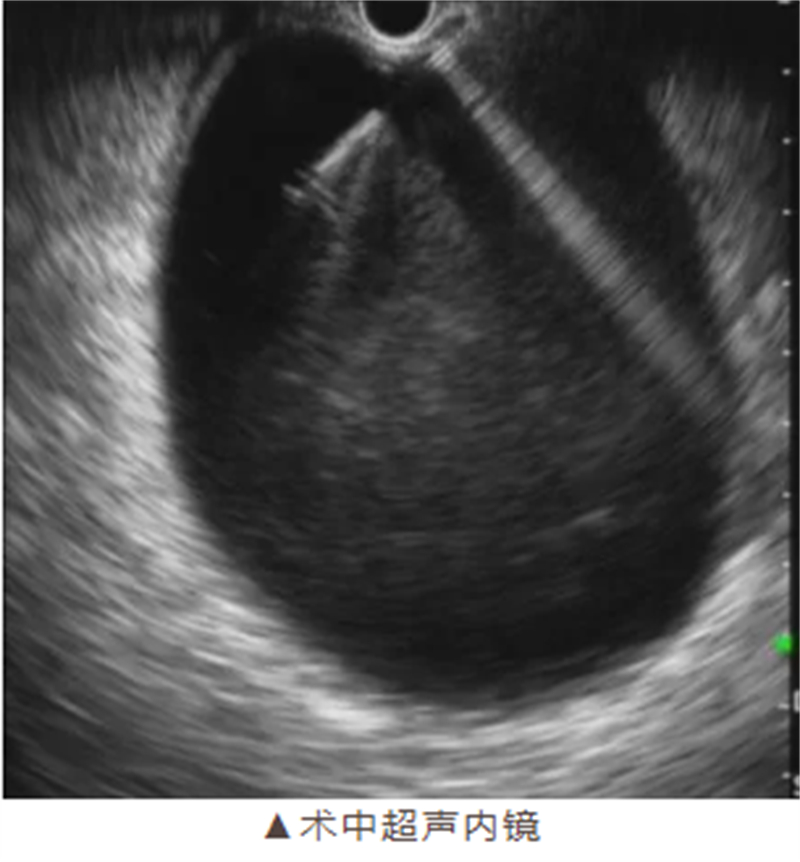

手術(shù)如期進(jìn)行,在麻醉科團(tuán)隊(duì)的密切配合下,消化病肝膽胰疾病診療中心手術(shù)團(tuán)隊(duì)嫻熟地操作超聲內(nèi)鏡,準(zhǔn)確定位囊腫位置,避開(kāi)重要血管和器官,成功完成穿刺引流并植入支架。整個(gè)手術(shù)過(guò)程僅耗時(shí)約40分鐘,術(shù)中無(wú)出血,展現(xiàn)了柳州市人民醫(yī)院醫(yī)療團(tuán)隊(duì)高超的技術(shù)水平和專業(yè)素養(yǎng)。

超聲內(nèi)鏡引導(dǎo)下的穿刺引流術(shù)則具有獨(dú)特優(yōu)勢(shì)。它利用實(shí)時(shí)超聲引導(dǎo),精準(zhǔn)定位囊腫位置,避開(kāi)重要血管和器官,通過(guò)自然腔道入路進(jìn)行穿刺引流,體表無(wú)創(chuàng)口,大大降低了手術(shù)風(fēng)險(xiǎn)和患者的痛苦。同時(shí),留置支架還能顯著降低復(fù)發(fā)率,使患者術(shù)后能夠迅速恢復(fù)進(jìn)食和正常生活。